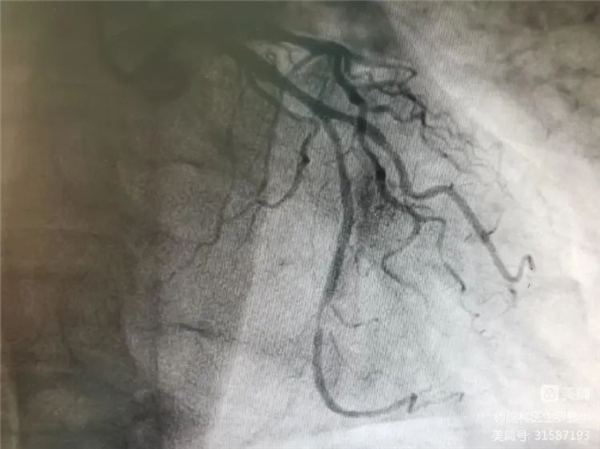

冠脈造影證實左旋支重度狹窄

釋放冠脈球擴支架

支架植入后狹窄完全解除